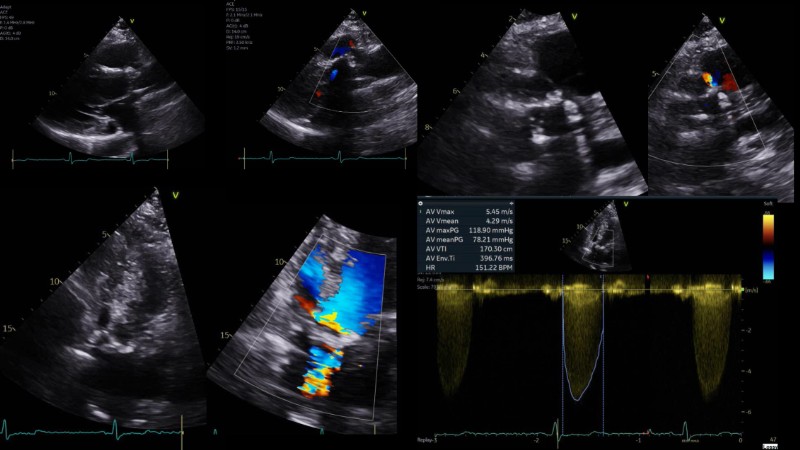

This session explores the evolving landscape of transcatheter aortic valve implantation (TAVI) with a focus on supra-annular valve technology. It covers techniques for achieving commissural alignment, considerations for small aortic annuli, and advantages in treating bicuspid aortic valve disease, supported by clinical data and illustrative cases.